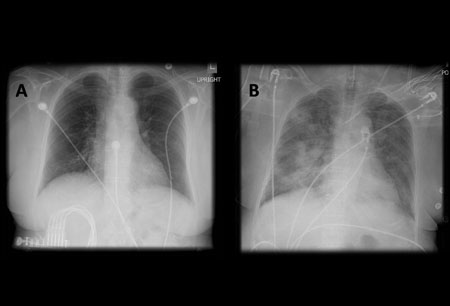

La aspiración de bario debe confirmarse mediante radiografía de tórax.[70][71][72][Figure caption and citation for the preceding image starts]: A. Radiografía portátil de tórax en posición erguida antes de la aspiración; B. Radiografía de tórax 1 hora después de la aspiración, en la que se muestran infiltrados alveolares difusos bilaterales, peores en las bases del lado derechoDe la colección del Dr. Henri Colt [Citation ends].